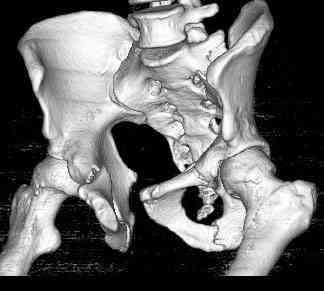

Уважаемые коллеги! опять вопрос по повреждению таза. Больной получил производственную травму 10 дней назад - удар балкой около 3 тонн в область верхней трети правого бедра и лона.

Был диагностирован перелом "типа бабочки" и повреждение уретры. Сделана цистостома. У насв отделении 3 дня. Имеется огромная флюктуирующая гематома с "галифе"-образной деформацией обеих бедер. Пнкционно эвакуировали в несколько приемов из подфасциальных полостей на бедрах около 3 литров геморрагического отделяемого с последующей эластической компрессией. При пункциях выявлено сообщение полостей на бедрах - видимо через поравннуюдиафрагму дна и полость таза - при удалении крови справа уменьшался объем левого бедра. Какой то активности проявялять покабоимся - аппаратная фиксация через отслоенные ткани представляется чреватой нагноением, открытая фиксация в условиях такой гематомы тоже не радует. Хотелось бы услышать ваше мнение

18.12. - отдельное спасибо еще раз А.В.Рункову- больного оперировали (А.В.Рунков) - произведен остеосинтез аппаратом - фиксация за крылья, два стержня в лонные кости и репозиция (почти полная) снимки будут чуть позже.

Дренировали отслойки на бедрах с их санацией. В правой ягодичной области сформировалась зона некроза. Больной "подвешен" за аппарат.